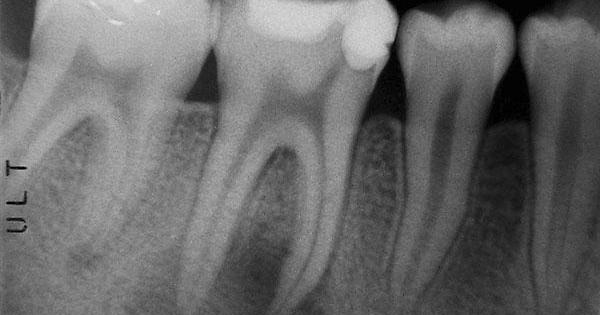

trattamento-endodonticoL’endodonzia è la scienza medica che, nell’ambito del’odontoiatria, si occupa dei tessuti interni del dente, le patologie e i trattamenti correlati. Nel momento in cui questi tessuti e quelli che circondano la radice si ammalato a causa di eventi curiosi,traumi o infezioni parodontali, il trattamento endodontico permette di salvare il dente. Tale trattamento si rende necessario quindi quando la polpa dentale si infiamma o si infetta. La polpa dentale contenuta all’interno dei denti svolge un ruolo fondamentale, trattadosi di un tessuto altamente specializzato coistituito da arterie, vene,terminazione nervose e cellule connettivali. Essa nell’età dello sviluppo ha la funzione di creare la struttura classificata portante del dente mentre nell’adulto, ad accrescimento avvenuto, la polpa dentale assotigliata e confinata all’ interno della camera pulpare e nei canali particolari, svolge una funzione di difesa e di diramazione della dentina. Una scarsa igiene orale con conseguente accumulo di placca batterica comporta la decalcificazione e successiva distruzione dei tessuti duri del dente per l’azione dei microorganismi presenti al’interno della placca batterica stessa; se non si interviene tempestivamente con la rimozione della carie la cavità prodotta si approfondisce fino ad arrivare alla camera pulpare con invasione dei batteri e delle loro tossine a carico della polpa dentale, con trasformazioni irreversibili causate daall’infezione. L’endodonzia quindi mira alla conservazione dei denti che hanno ricevuto un grave danno della loro struttura a causa dell’infezione e della successiva necrosi della polpa con ripercussioni acute o croniche dei tessuti circostanti e con sintomatologie spesso dolorose. Il trattamento in questa fase avanzata non comporta solo la rimozione del tessuto dentale cariato ma l’asportazione della polpa dentale necrotica o infetta, sia all’interno della camera pulpare sia all’interno delle radici. Tale procedimento noto come devitalizzazione si avvale ad oggi di numerosi strumenti che permettono al clinico di eseguire al meglio un trattamento canalare, eliminando completamente la polpa infetta residua sino all’apice del dente. Previa anestesia locale, il campo operatorio viene isolato mediante diga di gomma, ausilio imprescindibile per poter ottenere un ottimo risultato in quanto permette di isolare il dente dal resto della cavità orale senza consentire ulteriori contaminazioni batterica;allo stesso modo ci consente di utilizzare in tutta sicurezza disinfettanti e detergenti fondamentali per eliminare dai canali tutti i residui batterici creando quindi all’interno del dente un ambiente totalmente asettico. Si esegue quindi l’apertura della camera pulpare e il successivo accesso ai canali radicolari, poi mediante l’utilizzo di un rivelatore apicale si stabilisce l’esatta lunghezza della radice da trattare. Successivamente si passa alla strumentazione dei canali mediante utilizzo di strumenti endodontici meccanici allo scopo sia di eliminare completamente residui pulpari infetti sia di creare allo stesso tempo una forma delle pareti adatta ad una completa otturazione definitiva dei canali. Fondamentale in questa fase di preparazione l’utilizzo, in alternanza agli strumenti endodotici, di ipoclorito di sodio per eliminare tutta la componente organica e di rc prepp per quella inorganica. Completata la preparazione dei canali radicolari si segue la chiusura,  per tutta la lunghezza, mediante guttaperca; un materiale termoplastico che in concomitanza del cemento canalare garantisce un perfetto sigillo apicale. Una volta completata la devitalizzazione il dente é pronto per essere ricostruito, ristabilendo  quindi la forma della corona dentale che permette al dente stesso di riprendere completamente la sua funzione. É importante però ricordare che non essendo più un dente vitale, quindi idratato e nutrito dalla polpa, risulta  essere più fragile  e quindi facilmente soggetto a frattura a seguito dei traumi masticatori; é compito del clinico consigliare il paziente di proteggere il dente devitalizzato mediante la sua ricopertura con corona dentale.   Ambulatorio dentistico Zr Dental del dott. Alberto Ziliotto - Sito: www.odontoiatraziliotto.it